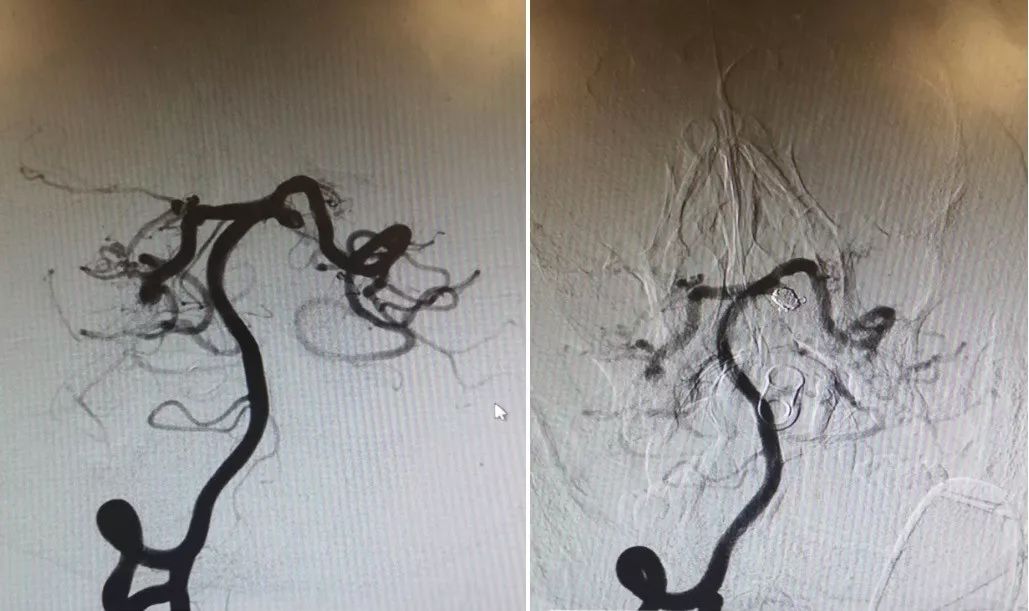

8年前动脉瘤治疗前后DSA(图2)

图2